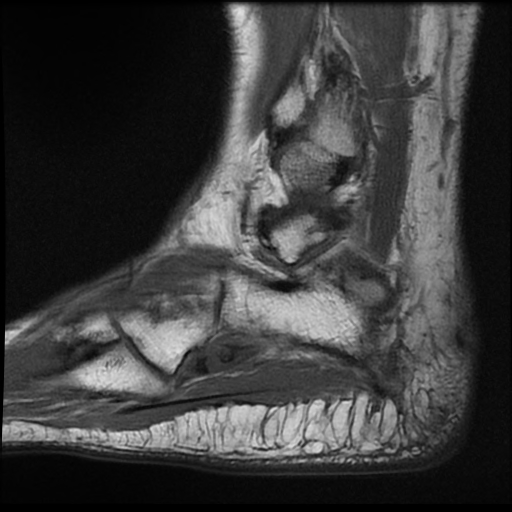

Painful os peroneum, fracture, diastasis. Fractures of the os peroneum present as pain localized on the lateral aspect of the foot resulting from direct trauma, muscle contraction, inversion injuries or chronic overuse injuries. Sx often mild, patients usually present with sprained ankle complaint.

X ray shows irregular, fragmented and possibly spread out appearance of osperoneum with soft tissue swelling in.

Fracture of the os peroneus with retraction of the peroneus longus tendon can lead to weakness, instability, and progressive foot deformity. Hiroyuki fujioka1, , takeshi kokubu2, takeshi makino2, issei nagura2, toshihisa maeda2, masahiro. Painful os peroneum, fracture, diastasis. Surgical excision and repair of peroneus longus tendon or tenodesis to peroneus brevis. Os peroneum treatment, etiology, epidemiology, natural history, anatomy, symptoms, xrays small accessory bone proximal to the base of the 5th metatarsal within the substance of peroneus longus. Subcutaneous peroneus longus tendon rupture associated with os peroneum fracture. Most common fracture at base of 5th metatarsal. Os peroneum is an accessory bone (ossicle) located at the lateral side of the tarsal cuboid, proximal to the base of 5th metatarsal, commonly mistaken for a fracture. Proposed treatment strategies for fracture of the os peroneum include. Brigido mk, fessell dp, jacobson ja, et al. Fracture of the os peroneum is relatively rare, and a stress fracture of the os peroneum is even rarer. Avulsion fracture of the os peroneum with pull of the. Fractures of the os peroneum are rare. Cureus accessory ossicles of the foot and ankle. Fractures of the os peroneum present as pain localized on the lateral aspect of the foot resulting from direct trauma, muscle contraction, inversion injuries or chronic overuse injuries. 578 x 430 jpeg 28 ΠΊΠ±. Fractures of the os peroneum present as pain localized on the lateral aspect of the foot resulting from direct trauma, muscle contraction, inversion injuries or chronic overuse injuries.